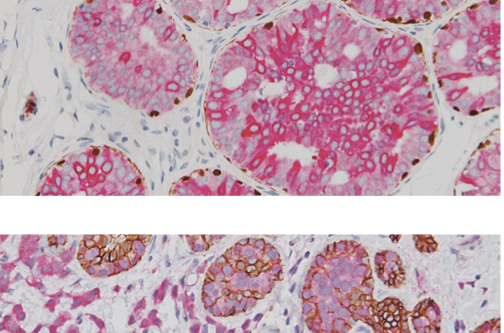

Inmunohistoquímica